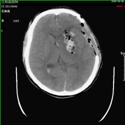

2).颅后窝血肿术前 术后